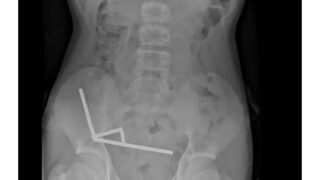

VIP 大腸内視鏡検査してるんだが

エッヂ 初大腸検査ワイ、準備が辛すぎる

なんG 悲報ワイ痔のため大腸カメラやったら潰瘍性大腸炎と診断